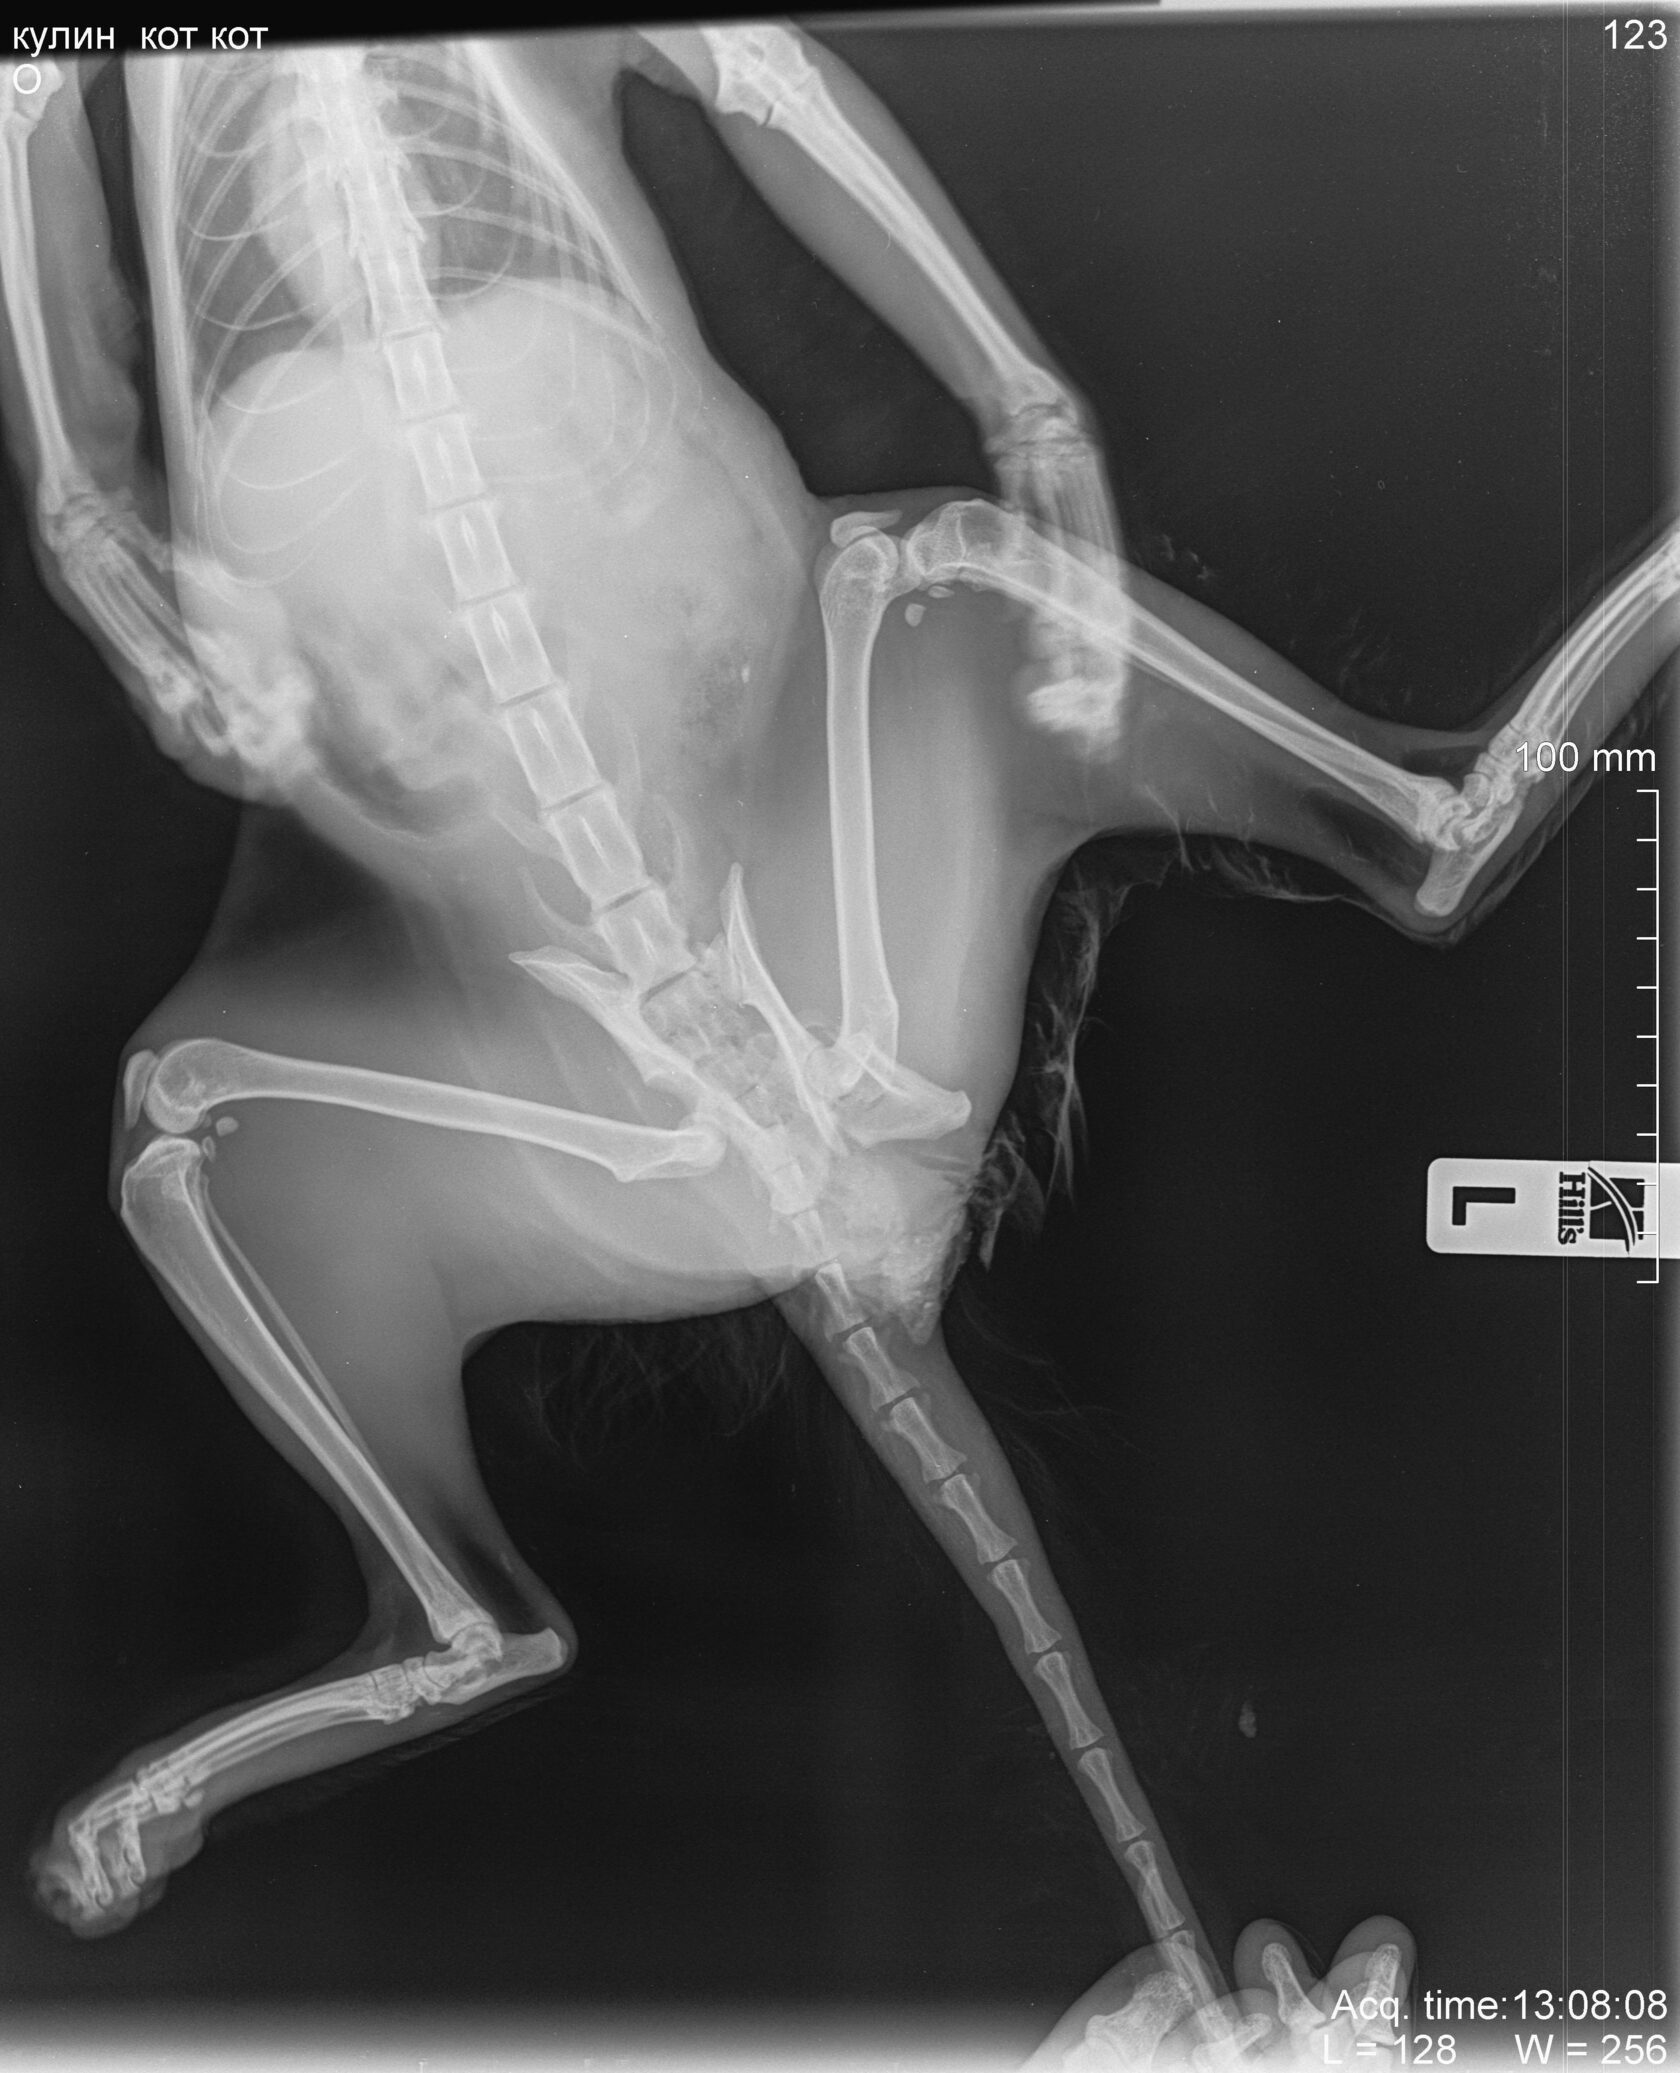

Рентгенограмма в вентродорсальной проекции таза, разрыв крестцово-подвздошного сочленения, перелом таза, вывих тазобедренного сустава вследствие падения с высоты.